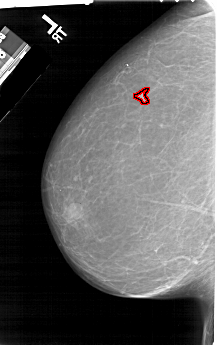

A_1204_1.RIGHT_CC

LEFT_CC LINES 6541 PIXELS_PER_LINE 4111 BITS_PER_PIXEL 12 RESOLUTION 43.5 OVERLAY

FILE: A_1204_1.LEFT_CC.OVERLAY

TOTAL_ABNORMALITIES 1

ABNORMALITY 1

LESION_TYPE MASS SHAPE IRREGULAR MARGINS ILL_DEFINED

ASSESSMENT 4

SUBTLETY 3

PATHOLOGY MALIGNANT

TOTAL_OUTLINES 1

BOUNDARY